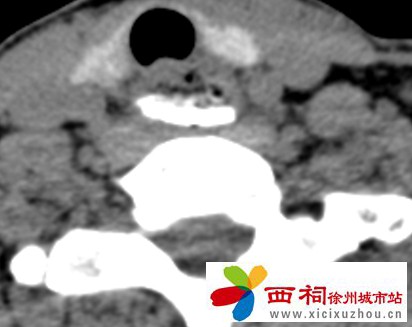

接诊后,沛县人民医院立即开启绿色通道。耳鼻喉科医生第一时间为患者安排相关检查,影像结果显示:食管上段异物滞留,伴有穿孔风险!若发生食管穿孔,可能引发严重感染,直接威胁患者生命,情况十分危急。

微信图片_2025-10-14_144235_630.jpg